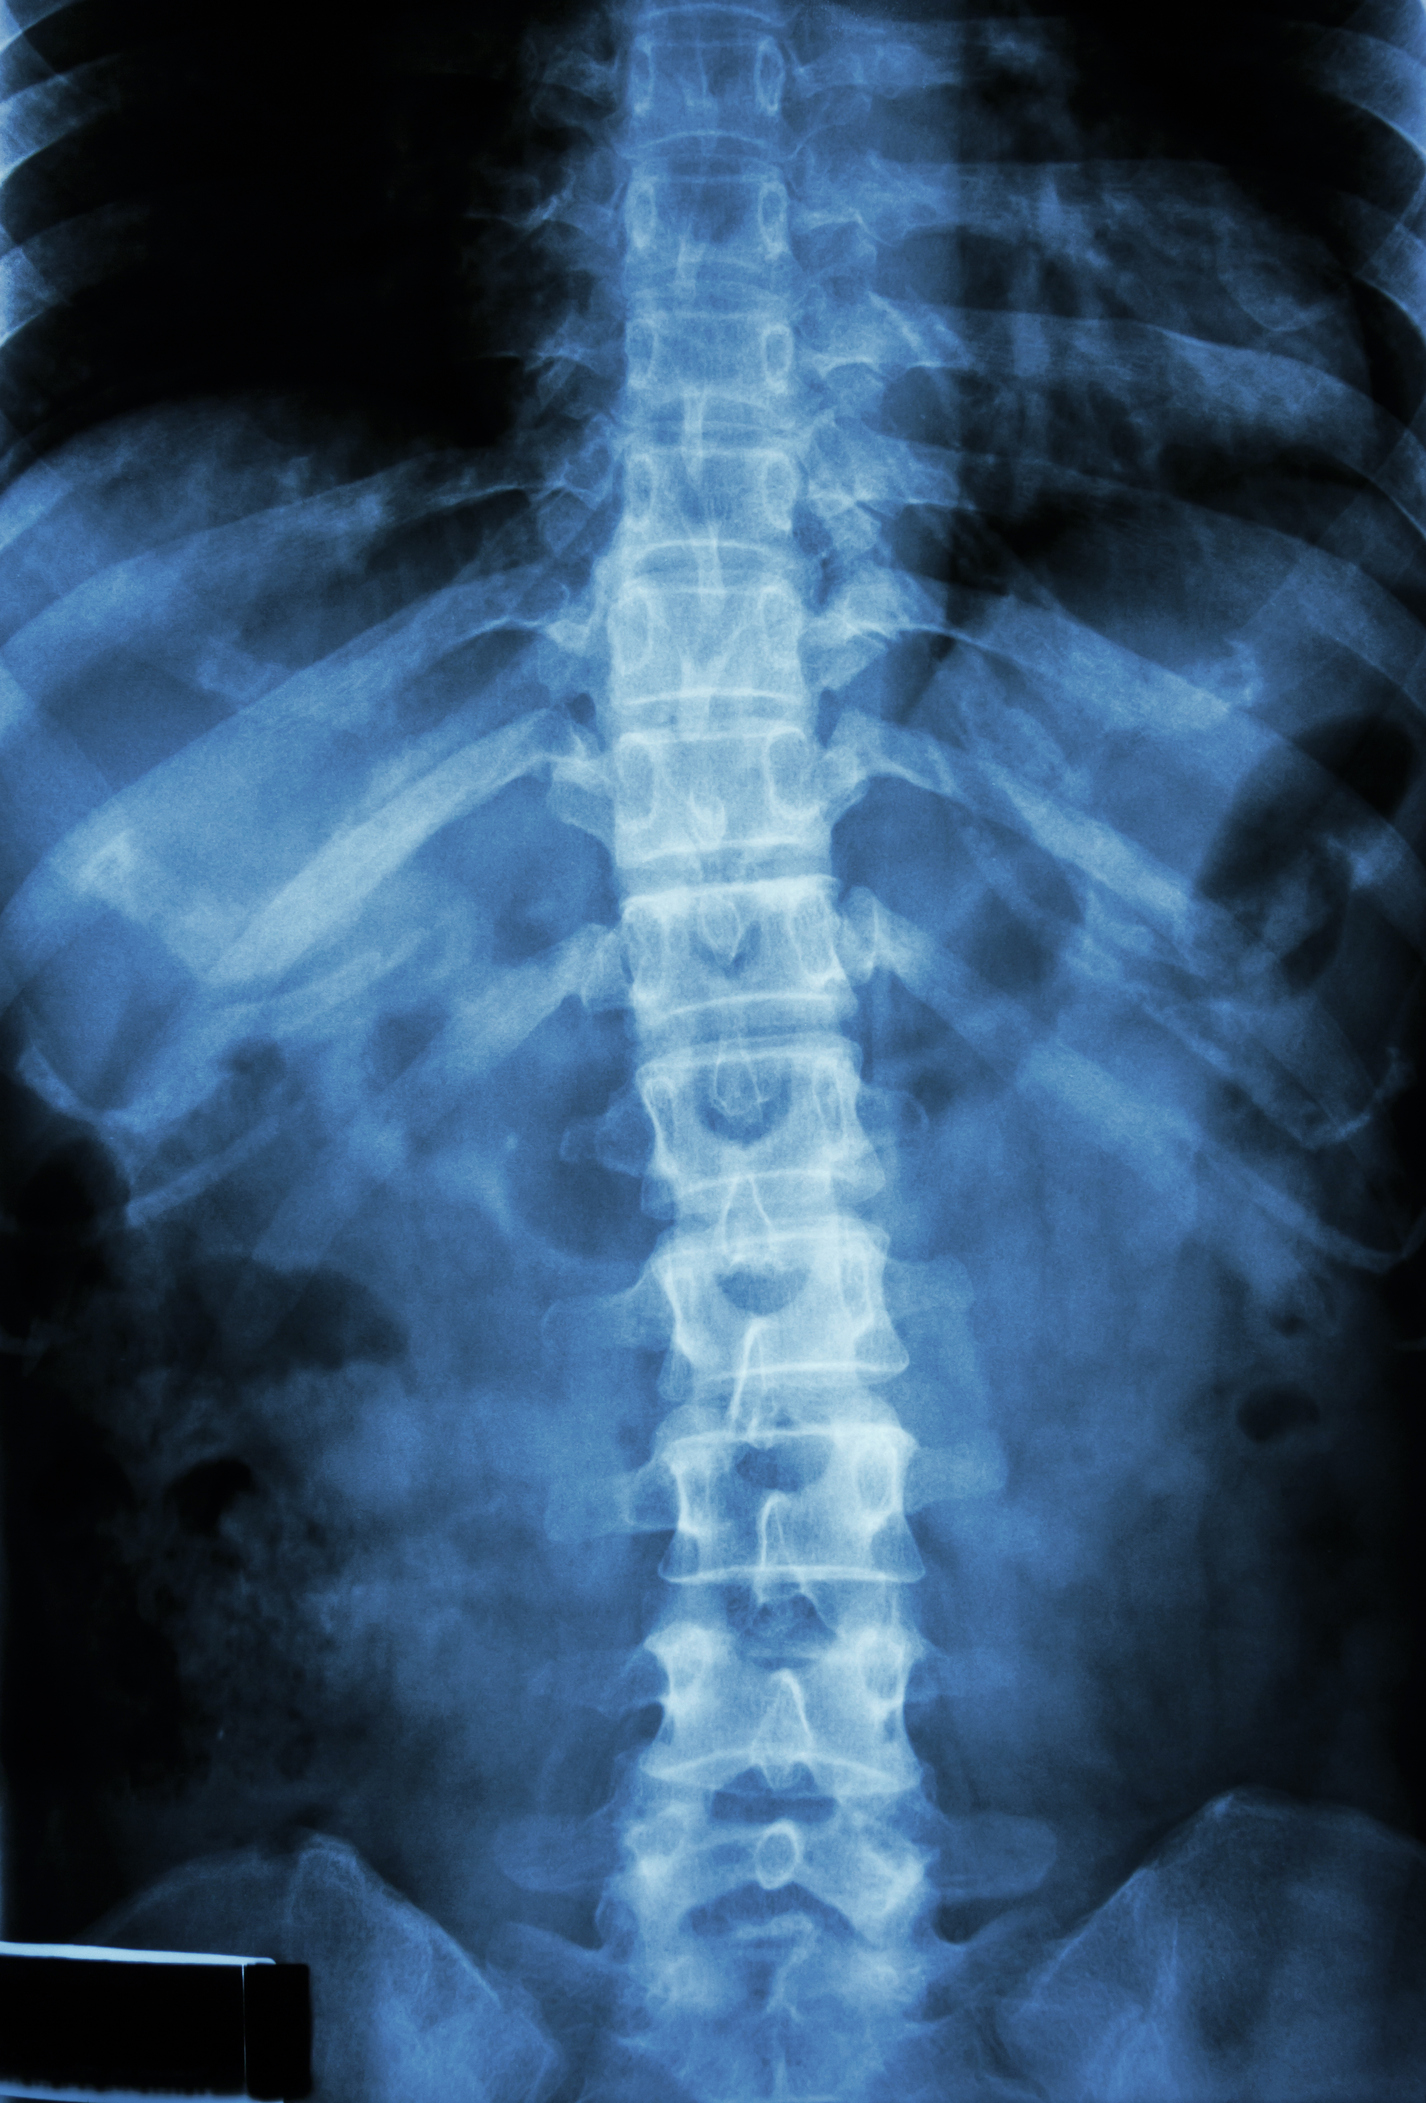

26-year-old Jered Chinnock injured his spinal cord at the sixth thoracic vertebrae three years ago. He could not move or feel anything lower than the middle of his back, and was diagnosed with a motor complete spinal cord injury.

Next, the team implanted an electrode below the injured area in the epidural space, close to the spinal cord, and a computer-controlled device just under the patient’s abdominal skin. The FDA gave permission to the Mayo Clinic for this off-label use of the device, which controls the transmission of an electrical current to the spinal cord, which in turn allowed the patient to create movement in his muscles.